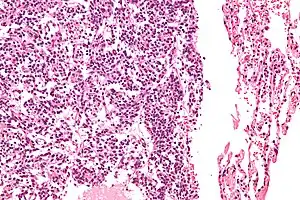

| Micrograph of a typical pulmonary carcinoid tumour. | |

The definitive diagnosis is rendered by a microscopic examination, after excision. Typical carcinoids have cells with stippled chromatin and a moderate quantity of cytoplasm. They typically have few mitoses and lack necrosis. By definition, they are greater than 4 mm in largest dimension; smaller lesions are referred to as pulmonary carcinoid tumourlets.